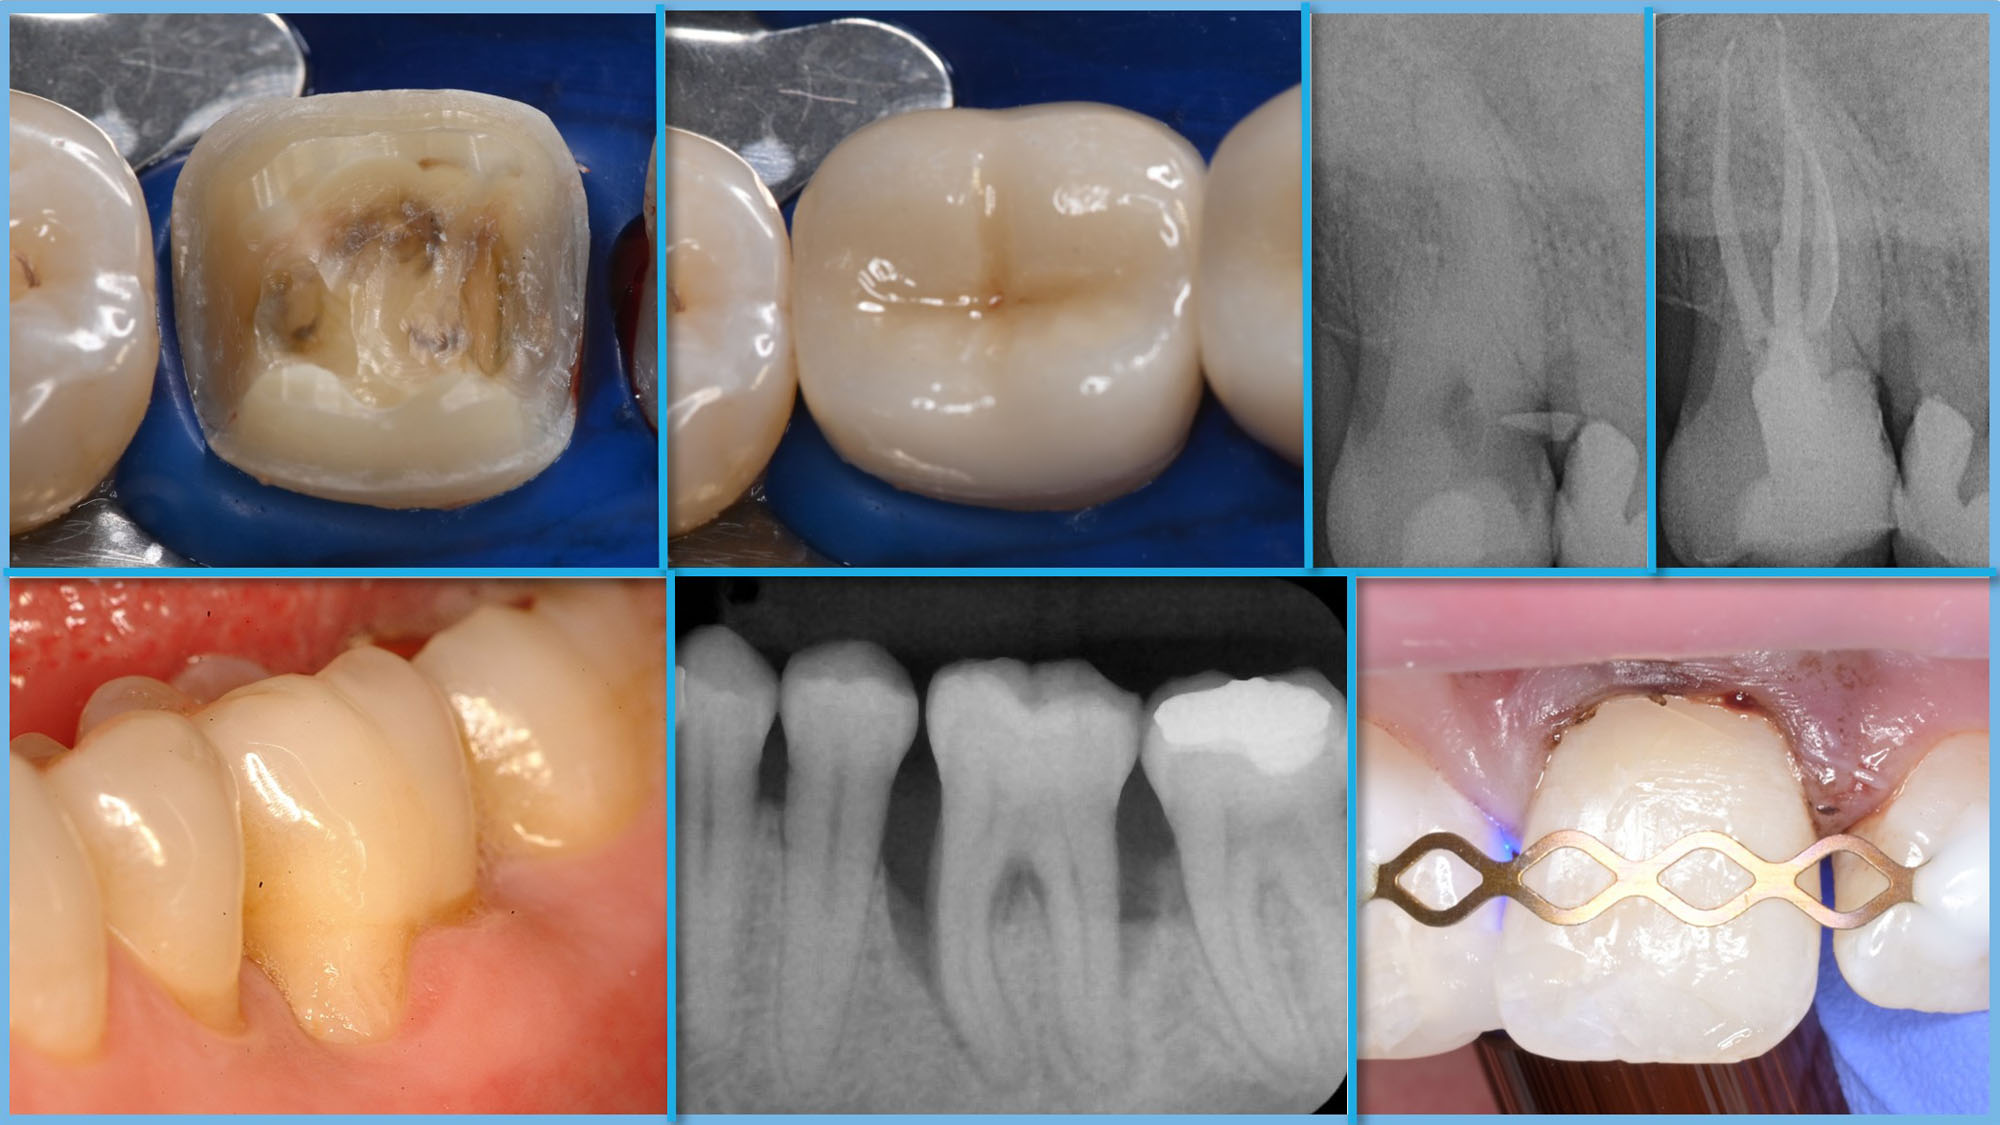

Der Studiengang Zahnerhaltung ist ein berufsbegleitender Weiterbildungsstudiengang mit dem Abschluss Master of Science (M.Sc.). Er bietet eine klinisch orientierte Ausbildung nach den aktuellsten evidenzbasierten Standards und entsprechend der Leitlinien der wissenschaftlichen Fachgesellschaften. Während des Studiums werden die Bereiche der Restaurativen Zahnerhaltung, der Parodontologie, der Endodontologie sowie der Präventiv- und Kinderzahnmedizin in Theorie und Praxis vermittelt. Die Regelstudienzeit beträgt 5 Semester.

Zentraler Bestandteil des Studiengangs ist die Arbeit an und mit Patientenfällen aus der Praxis. Die praktische Tätigkeit setzt jedoch die Einbettung der klinischen Fälle in den aktuellen wissenschaftlichen Kontext voraus, der in den entsprechenden Modulen erarbeitet wird.

Dabei wird in Vorlesungen Wissen vermittelt, das deutlich über die während des Studiums der Zahnmedizin vermittelten Grundlagen hinausreicht. Regelmäßige Fallpräsentationen und -besprechungen schulen den Transfer und ermöglichen den Austausch mit Kolleginnen und Kollegen. Die entsprechenden klinischen Fälle werden entsprechend eines Fallkataloges dokumentiert, als Präsentationen vorgestellt und gemeinsam diskutiert. Trainingskurse mit Demonstrationen und Hands-on-Übungen in Simulationen ergänzen die Lehrformate und ermöglichen die Weiterentwicklung Optimierung klinischer Techniken und Fertigkeiten.

In den ersten vier Semestern werden die Fächer der Zahnerhaltung gelehrt: Restaurative Zahnerhaltung, Parodontologie, Endodontie, Präventive und Kinderzahnmedizin. Im fünften Semester folgt die Masterarbeit. Während des Semesters finden jede Woche Vorlesungen und klinische Fallbesprechungen statt, die im Hybridformat durchgeführt werden. Das Hauptaugenmerk liegt auf der Patientenbehandlung, die in der eigenen Praxis durchgeführt wird. Dabei soll in jedem der vier Fächer ein vorgegebener Behandlungskatalog erfüllt werden. Die Fälle werden nach vorgegebener Form dokumentiert sowie in den Fallbesprechungen durchgenommen und diskutiert. Pro Semester gibt es jeweils freitagnachmittags 2-3 Hands-on Kurse, deren Termine vorab festgelegt werden.

Restaurative Zahnerhaltung, Parodontologie, Endodontie, Präventive und Kinderzahnmedizin.